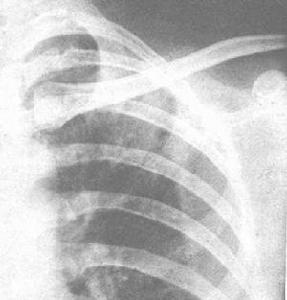

X線胸片顯示不呈段或葉性分布的周圍片狀陰影,常為雙側分布(“肺水腫反轉”表現)。糖皮質激素治療後48小時內症狀和X線表現可迅速消失。在同一局部可反覆發生,數年後變為纖維化或蜂窩狀改變。胸部X片顯示不呈段或葉性分布的周圍片狀陰影,常為雙側分布。糖皮質激素治療後48h內症狀和胸片可迅速消失。在同一局部可反覆發生,數年後變為纖維化或蜂窩狀改變。糖皮質激素治療效果顯著,常可恢復正常,因停藥較易復發,故全療程需在一年以上。

其他輔助檢查:X線表現:大葉實變、小葉浸潤、膿腫形成。大葉實變多位於右上葉,由於炎性滲出物量多,黏稠且重,故葉間裂呈弧形下墜。炎症浸潤中見膿腫,胸腔積液,少數呈支氣管肺炎。